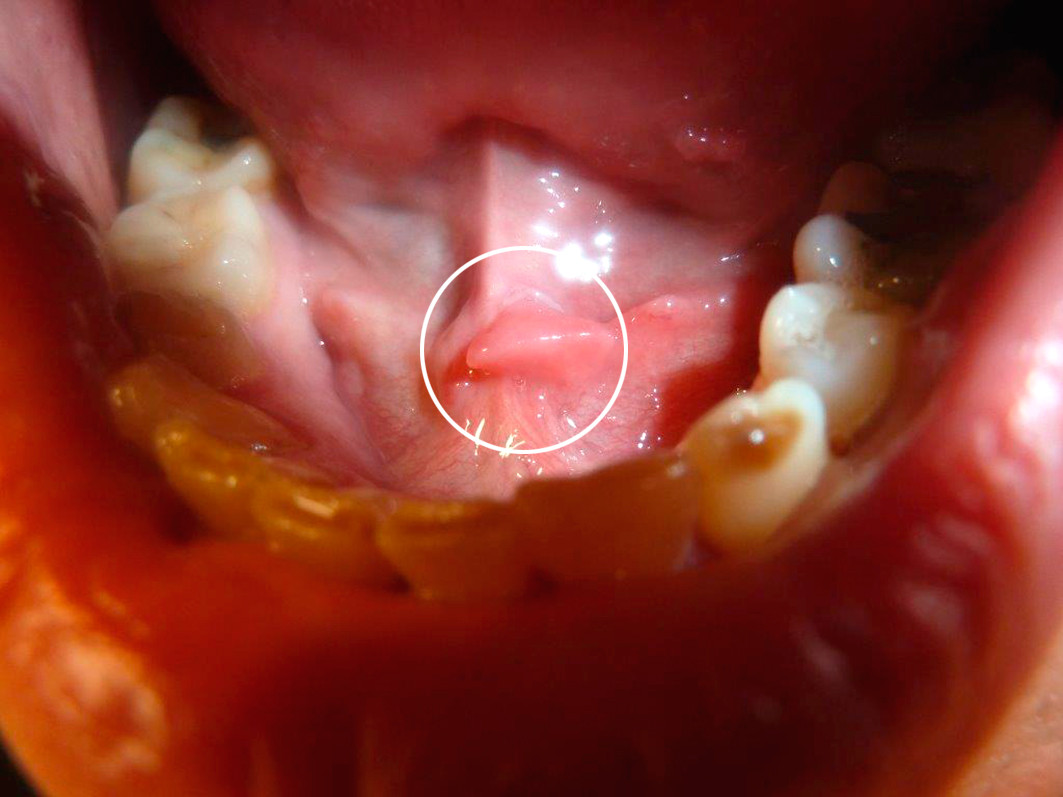

Ved undersøkelse var huden på glans penis og preputium sklerosert og hypopigmentert. Det var et 3 mm sår på frenulum (fig 1) og et 5 mm sår på scrotum (fig 2). Sårene var ikke indurert. Pasienten klaget over ømhet og svie ved prøvetaking. I høyre lyske ble det palpert en 1 cm stor uøm lymfeknute. Det ble også funnet et makuløst utslett på venstre underarm (fig 3) og en 2 mm hvitlig lesjon under tungen like ved den sublingvale karunkelen (fig 4).

Hos vår pasient var PCR-test positiv fra alle sår, selv fra en klinisk lite fremtredende oral slimhinneforandring. PCR-test av sår forårsaket av T. pallidum har en sensitivitet på 82 % og en spesifisitet på 95 % (8) og er et nyttig tillegg til serumprøver for diagnostikk av genitale, anale og orale lesjoner hos pasienter som kan ha vært utsatt for syfilissmitte. Ved primær syfilis vil man kunne få positiv PCR-test på penselpinne før det dannes antistoffer i serum. Dette kan gi pasienten tidlig avklaring og behandling og dermed hindre videre smitte.